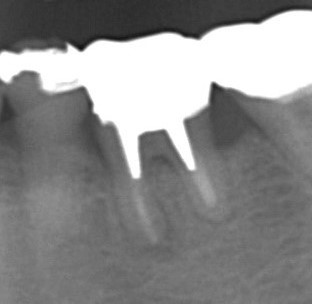

慢性根尖性歯周炎では、痛みや腫れなどの目立った症状はありませんが、レントゲン写真撮影をすると根の先に黒い影ができています。

この影の正体は、膿です。

根の周囲の病巣は、レントゲン写真ではわかっても直接目で見ることはできませんし、直接治療することもできません。

しかも、側枝というレントゲンに写らないような細い枝別れもあります。

きれいに割れていればレントゲン写真でわかるものですが、ヒビだけですと見つからないことも多いです。